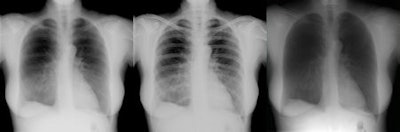

![]() |

| Image series demonstrates high-energy image (left), low-energy image (center), and soft-tissue image (right) produced by processing both images. |